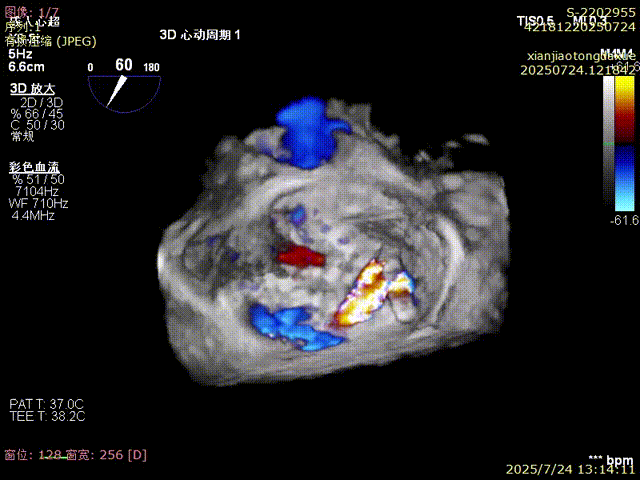

3D确认夹合位置

反流得到明显改善

3D视角下反流情况